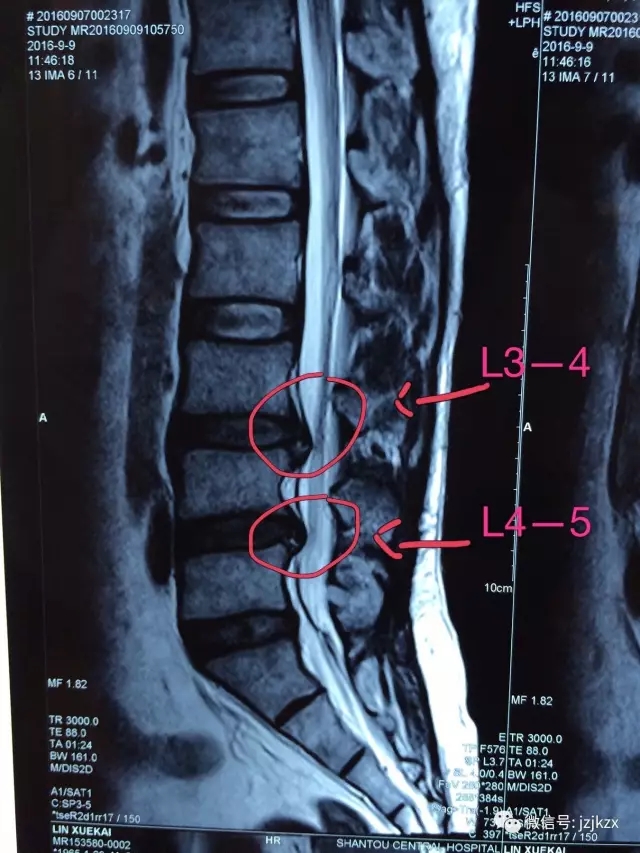

患者腰部肌群僵硬,L3—4,L4—5椎旁压痛明显,右侧臀部肌肉与大腿外侧明显压痛,直腿抬高试验左(一)右(➕),四字征左(一)右(➕),髋关节活动正常。

MR检查:C3/4,C4/5,C6/7椎间盘突出,C5/6左后突,局部椎管狭窄。L3/4,L5/S1椎间盘突出,局部椎管狭窄,髋关节X光检查无明显异常。